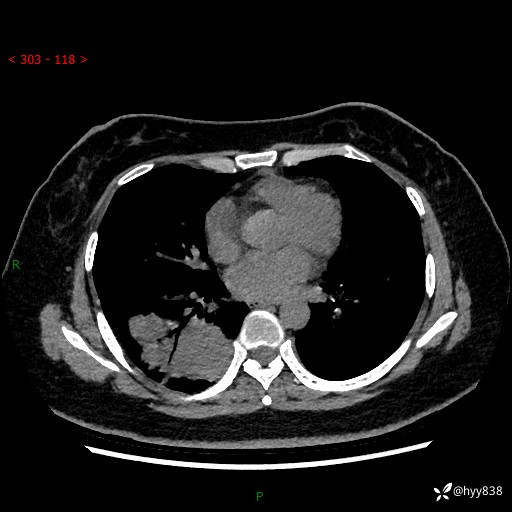

增强动脉期+静脉期